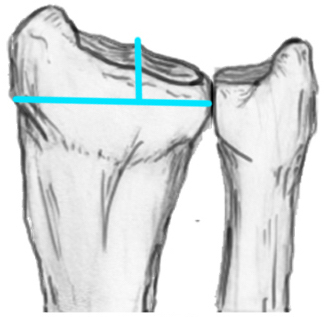

Distal Radius Angles

- radial volar tilt 11°

- radial inclination  22°

- radius is 11 mm longer than ulna

- ulna variance 2mm positive on average

Distal Radius NormalNormal Radial InclinationNormal Radial Length